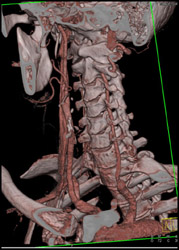

Superior Mesenteric Artery (SMA) Stenosis